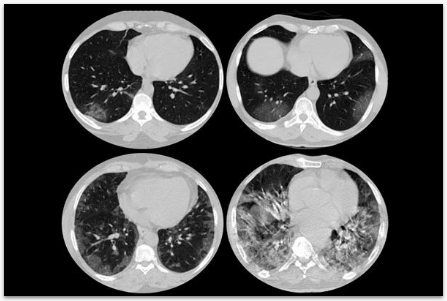

Algoritmos para análise de TC e RX para detecção de COVID-19, integrados à plataforma RadVid19.

Classificação de risco em cirurgias torácicas de câncer de pulmão usando dados clínicos e de imagem.